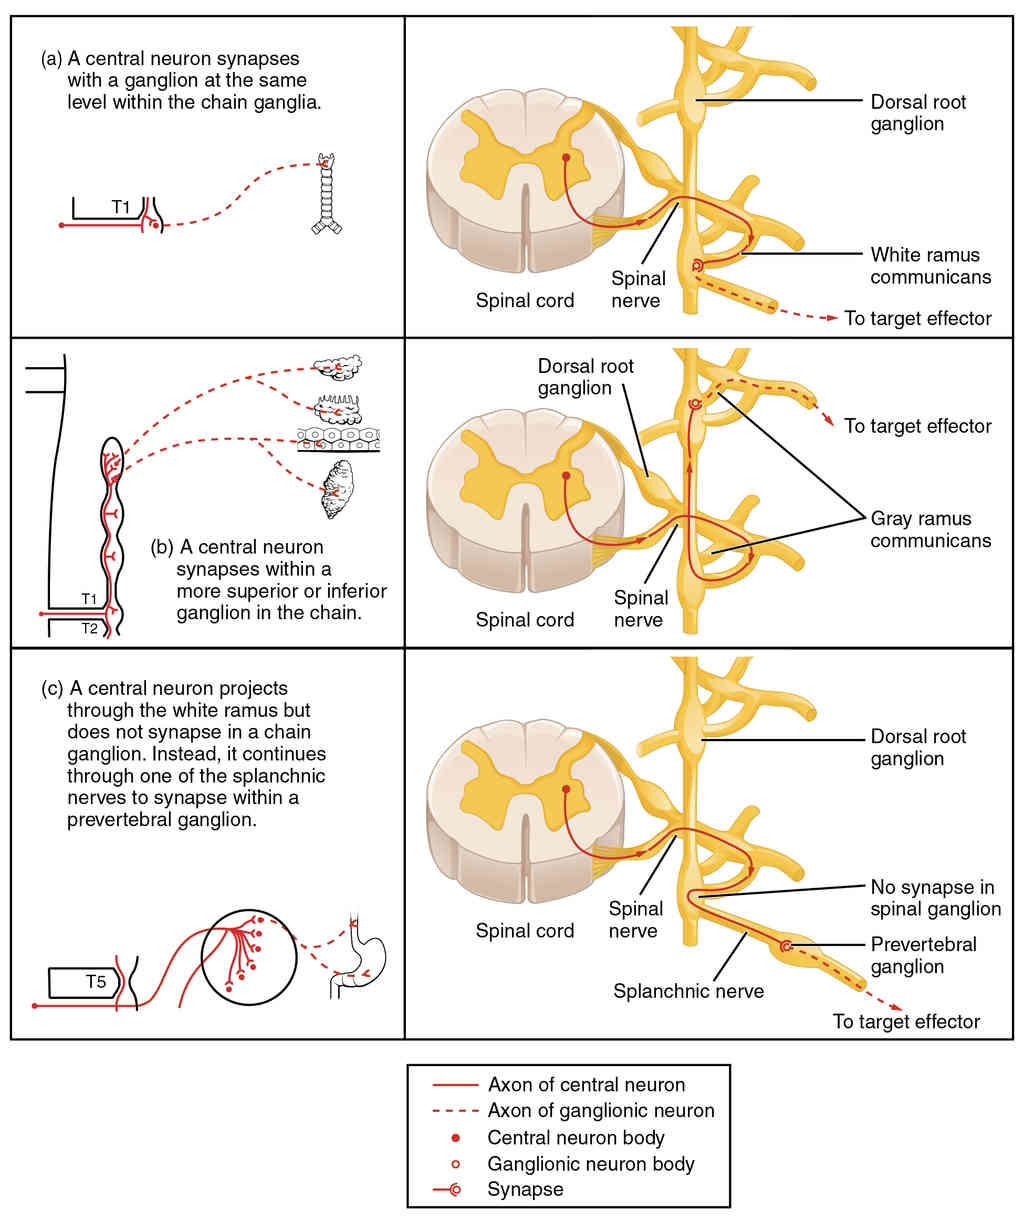

This page is under construction. For now, it is just a resource of the images found in the OpenStax Anatomy and Physiology Handbook. It wil slowly change into a revision tool. Each slide has a number. Use this to refer to the slide. When completed, it will have an unlabelled section, with labelled slides in parallel. On the unlabelled slides, write your answer and use the labelled slide to assess yourself. Keep track by also noting the number on each slide. Improvement at each attempt is important, more so than full marks on a first attempt.